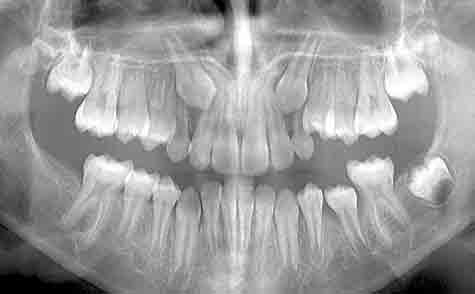

They assessed the initial position of the PDC on the PAN using the method first described by Ericson and Kurol. They based this around the following measurements.

Alpha angle: The angle formed by the long axix of the canine and the midline

D: The distance in mm from the canine tip to the occlusal plane

Sector: The mesiodistal crown position in sector 1-5. I have pasted in their diagram here.